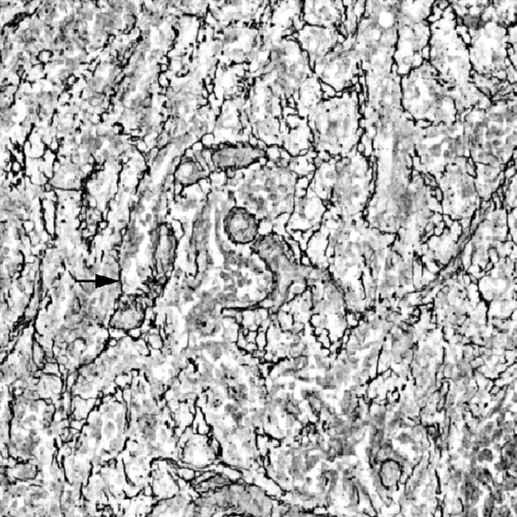

网状纤维(reticular fiber)网状纤维在疏松结缔组织中含量较少,纤维较细,有分支,彼此交织成网状。 用浸银法可将纤维染成黑色,故又称嗜银纤维 (argyrophilic fiber)。电镜观察,网状纤维具有等间距的 横纹结构,其化学成分也是胶原蛋白,和胶原纤维相似。网状纤维的嗜银性是由于包在原纤维上的糖蛋白 所致。

14、常规透明,中性树胶封固。 结果:网状纤维黑色,核红色,胶原纤维黄棕色。

网状纤维镀银染色 x100